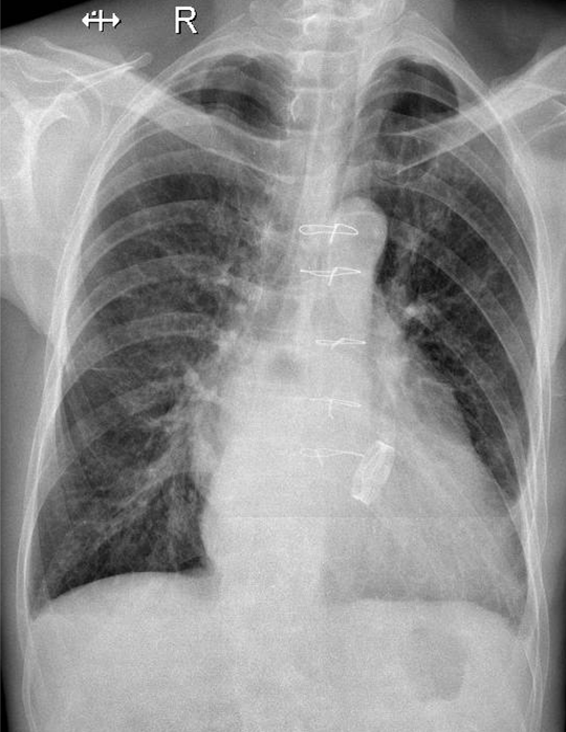

1-Thâm nhiễm mô kè rải rác hai phổi => Viêm phổi 2-Tim to 3-Chỉ cản quang kim loại dọc xương ức 4-Val tim nhân tạo